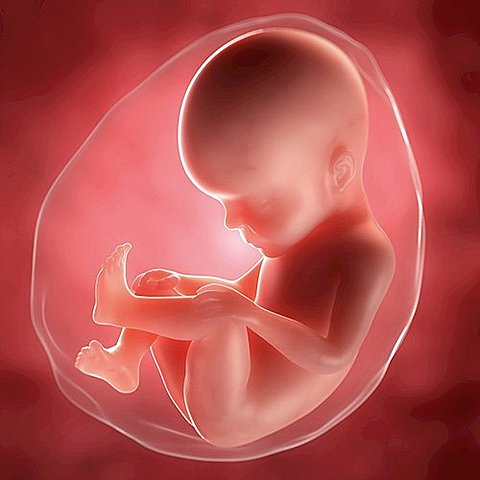

• Semana 9 "Empieza su movimiento"

Semana 9 "Empieza su movimiento"

En esta semana puede estirarse y moverse y su madre podría no sentirlo pero el percibe todas sus emociones sus órganos y cerebro se están desarrollando